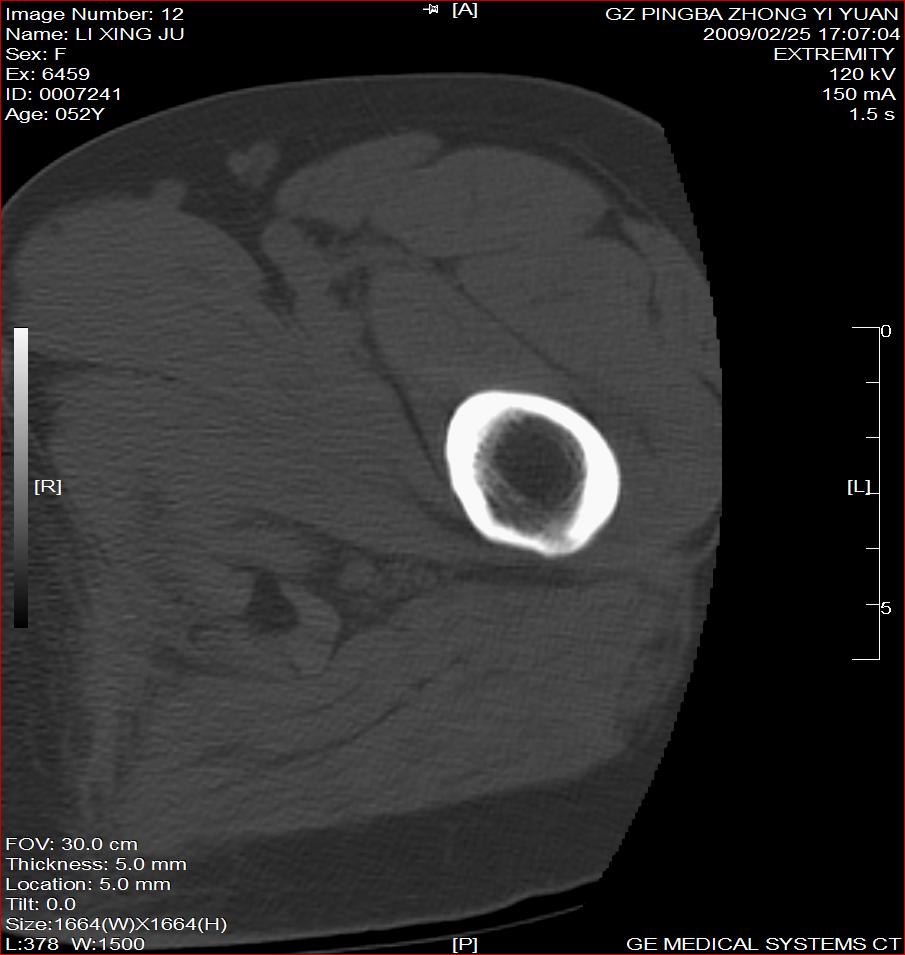

标题: CT18521:左大腿疼痛不适1+月 [打印本页]

标题: CT18521:左大腿疼痛不适1+月

考虑-----股骨骨化性纤维瘤可能性大,不除外---局限性骨纤

考虑:左股骨骨化性纤维瘤

考虑:骨纤或骨梗可能性大

考虑 左股骨骨化性纤维瘤。

骨梗塞

考虑骨化性纤维瘤可能性大